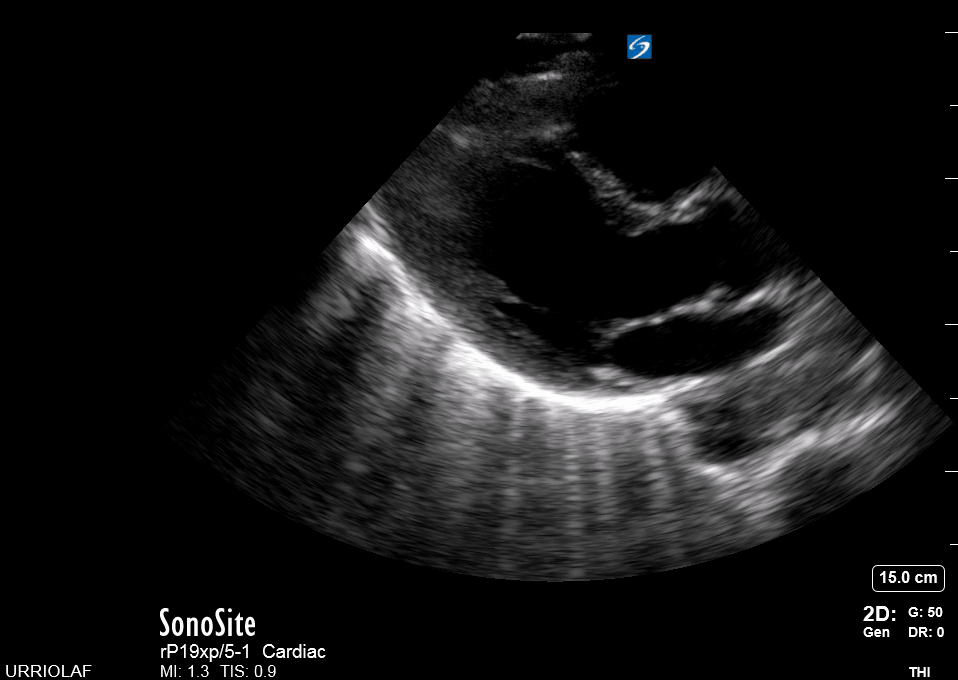

This view looks at the heart from the apex. When done properly, it achieves a horizontal cut of the heart that demonstrate all four chambers simultaneously. Consequently, its main utility is to assess the relationship between LV and RV. Beware, differentiating the chambers by ventricle size or thickness is not recommended, and it could lead to confusion in case of RV enlargement.

Place the transducer at the apex beat and angle it towards the right scapula. The correct image results from sliding the probe until the interventricular septum is in the middle of the screen, vertically dividing both sides of the heart. If using a cardiac preset, the probe’s marker points towards the patient’s left arm. Simpler, in this view, the probe notch should meet the marking on the screen, which is fundamental to avoid confusion.